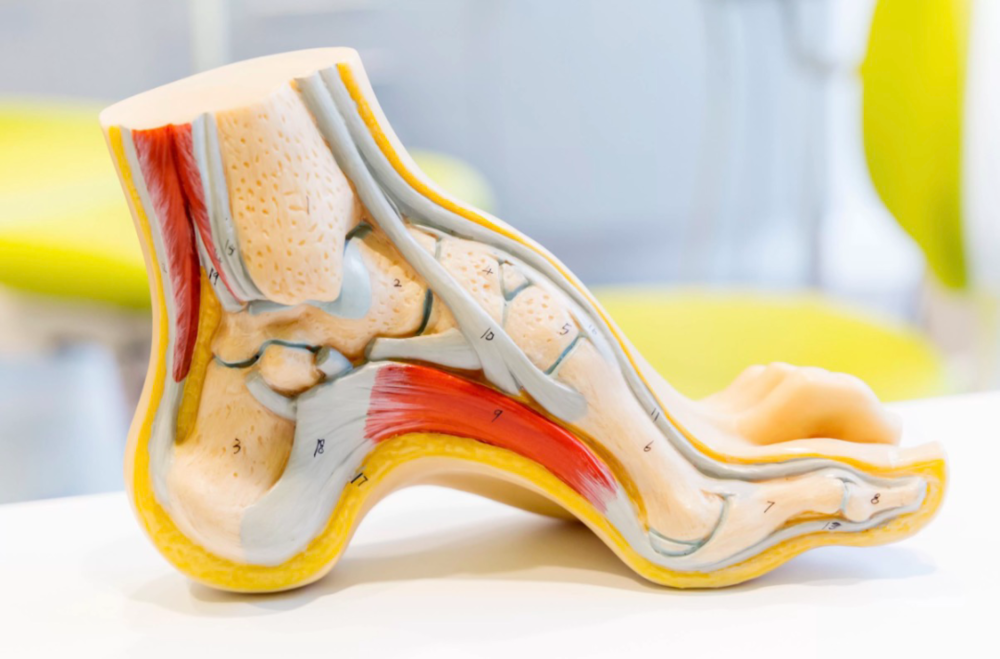

3条足弓,26块足骨,33个关节,超百条肌肉、肌腱、与韧带,共同构成了我们的足部。

足部模型

而对于运动健身者,足弓的重要性不言而喻。

一般提及的足弓其实由三部分构成:

内侧纵弓:也称为减震器。由跟骨、距骨、舟骨、三块楔骨及第1~3跖骨构成,位于足内侧缘。此弓曲度大,弹性强,适于跳跃并能缓冲震荡。

外侧纵弓:也称为稳定器。由跟骨、骰骨及第4、5跖骨构成,位于足外侧缘。此弓曲度小、弹性弱,主要与直立负重姿势的维持有关。

横弓:也称为推进器。由各跖骨的后部及跗骨的前部构成。此弓作用为稳定足底,并在行走时帮助身体向前推进。

足弓结构